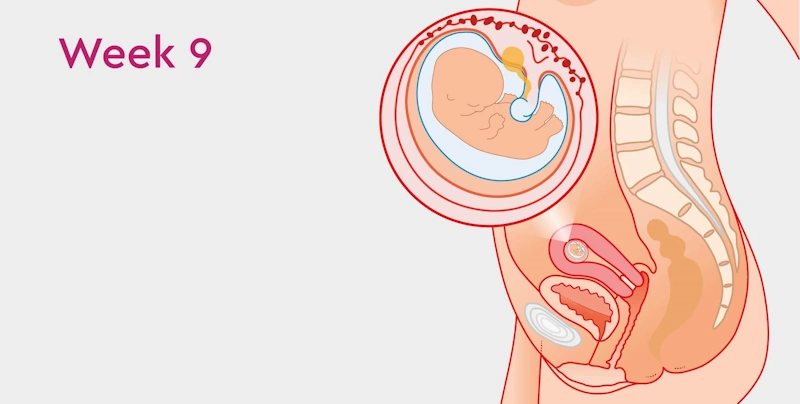

Fetal Development in Week 9

At week 9, your baby is no longer just an embryo — it’s officially called a fetus.

The transformation from a cluster of cells to a tiny, developing human is in full swing.

🫀 Size and Appearance

Your baby is about 2.5 cm long (about the size of a grape).

The head is large compared to the body, but soon proportions will balance.

Eyes, nose, mouth, and ears are forming — though eyelids remain closed.

Tiny arms and legs are visible, with fingers and toes starting to separate.

🧠 Internal Development

The nervous system continues to develop, allowing small reflexes and twitches.

The heart beats 160–170 times per minute, nearly double an adult’s rate.

Liver, spleen, and pancreas begin functioning, producing bile and insulin.

The placenta is forming and will soon take over nourishment duties from the yolk sac.

Lungs begin forming air passages that will later expand for breathing.

If you could see your baby via ultrasound this week, you might notice tiny arm movements — the very first signs of motion!